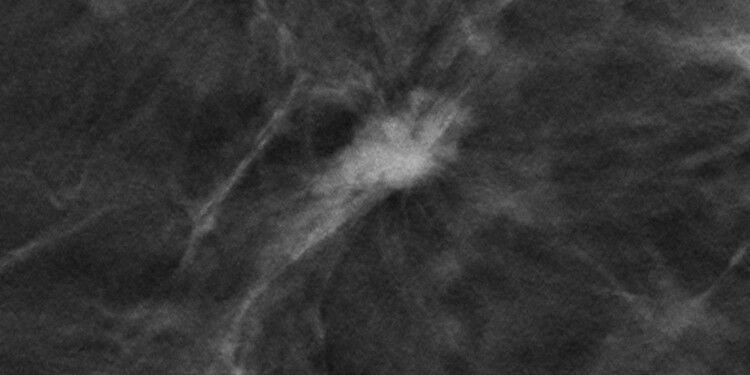

Digital breast tomosynthesis of the left breast showing a spiculated mass of increased density. Histology: Invasive lobular breast carcinoma grade 2. © Uni MS - ToSyMa

Further TOSYMA analysis underpins advantages of DBT+SM use compared to the previous screening standard. Digital breast tomosynthesis of the left breast showing a spiculated mass of increased density. Histology: Invasive lobular breast carcinoma grade 2. Uni MS - ToSyMa In diagnostics, finding more is not automatically better. Rather, it is about finding the right thing - especially in the case of such dangerous diseases as cancer. This is where early detection comes into play, but it can also have unwanted side effects: For example, there is a risk of also discovering non-aggressive tumors that lead to treatment - but would not have substantively impaired quality of life or become life-threatening in the course of the disease. Medicine speaks of overdiagnosis.